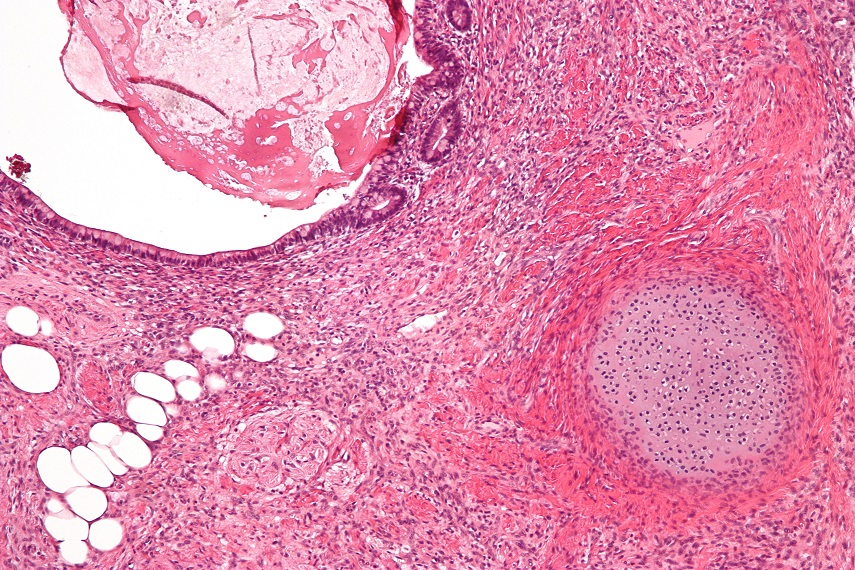

Кистозная тератома выглядит как гладкий крупный узел. При разрезе будут видны крупные кисты с различным содержимым (слизь, кашеобразная масса, мутная жидкость). В полостях можно обнаружить различные включения (костные, хрящевые, иногда бывает опухоль с волосами или зубами).

Солидная тератома имеет вид гладкого плотного или, наоборот, бугристого узла. При разрезе будет видна светло-серая, неоднородная, с небольшими кистами и включениями плотного характера, ткань. Включения могут быть из костной или хрящевой ткани.

Тератомы незрелые при разрезе представляют собой небольшие кисты светло-серого цвета, содержимое которых может состоять из незрелого эпителия, нейрогенного эпителия, хрящевой ткани и поперечнополосатых мышц.

Тератома яичника. Такой диагноз встречается чаще тератомы яичка. Среди всех новообразований яичника такой диагноз встречается в 20% случаев. В основном это узлы кистозного строения, но бывают и незрелые тератомы. Так как тератома яичника протекает часто бессимптомно, то, как правило, ее обнаруживают при диагностике другого заболевания. Обычно активизация этого вида опухоли приходится на периоды гормональной перестройки (период полового созревания, реже – при наступлении климакса). В удаленных яичниках можно найти различные включения – зубы, волосы.